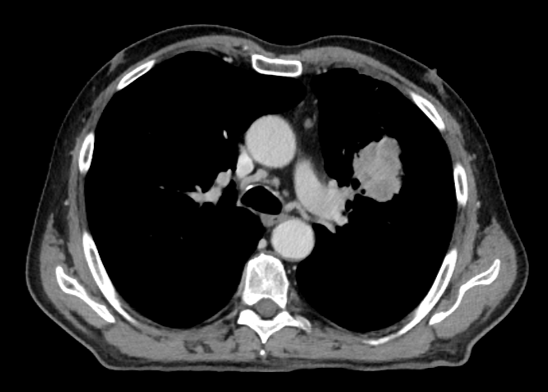

Řez plicemi z CT screeningu: CT plic z 11/2023 s nálezem trvající téměř kompletní remise (stacionární atelektáza plicního pole vlevo)

Obr 4. – CT plic z 11/2023 s nálezem trvající téměř kompletní remise (stacionární atelektáza plicního pole vlevo).